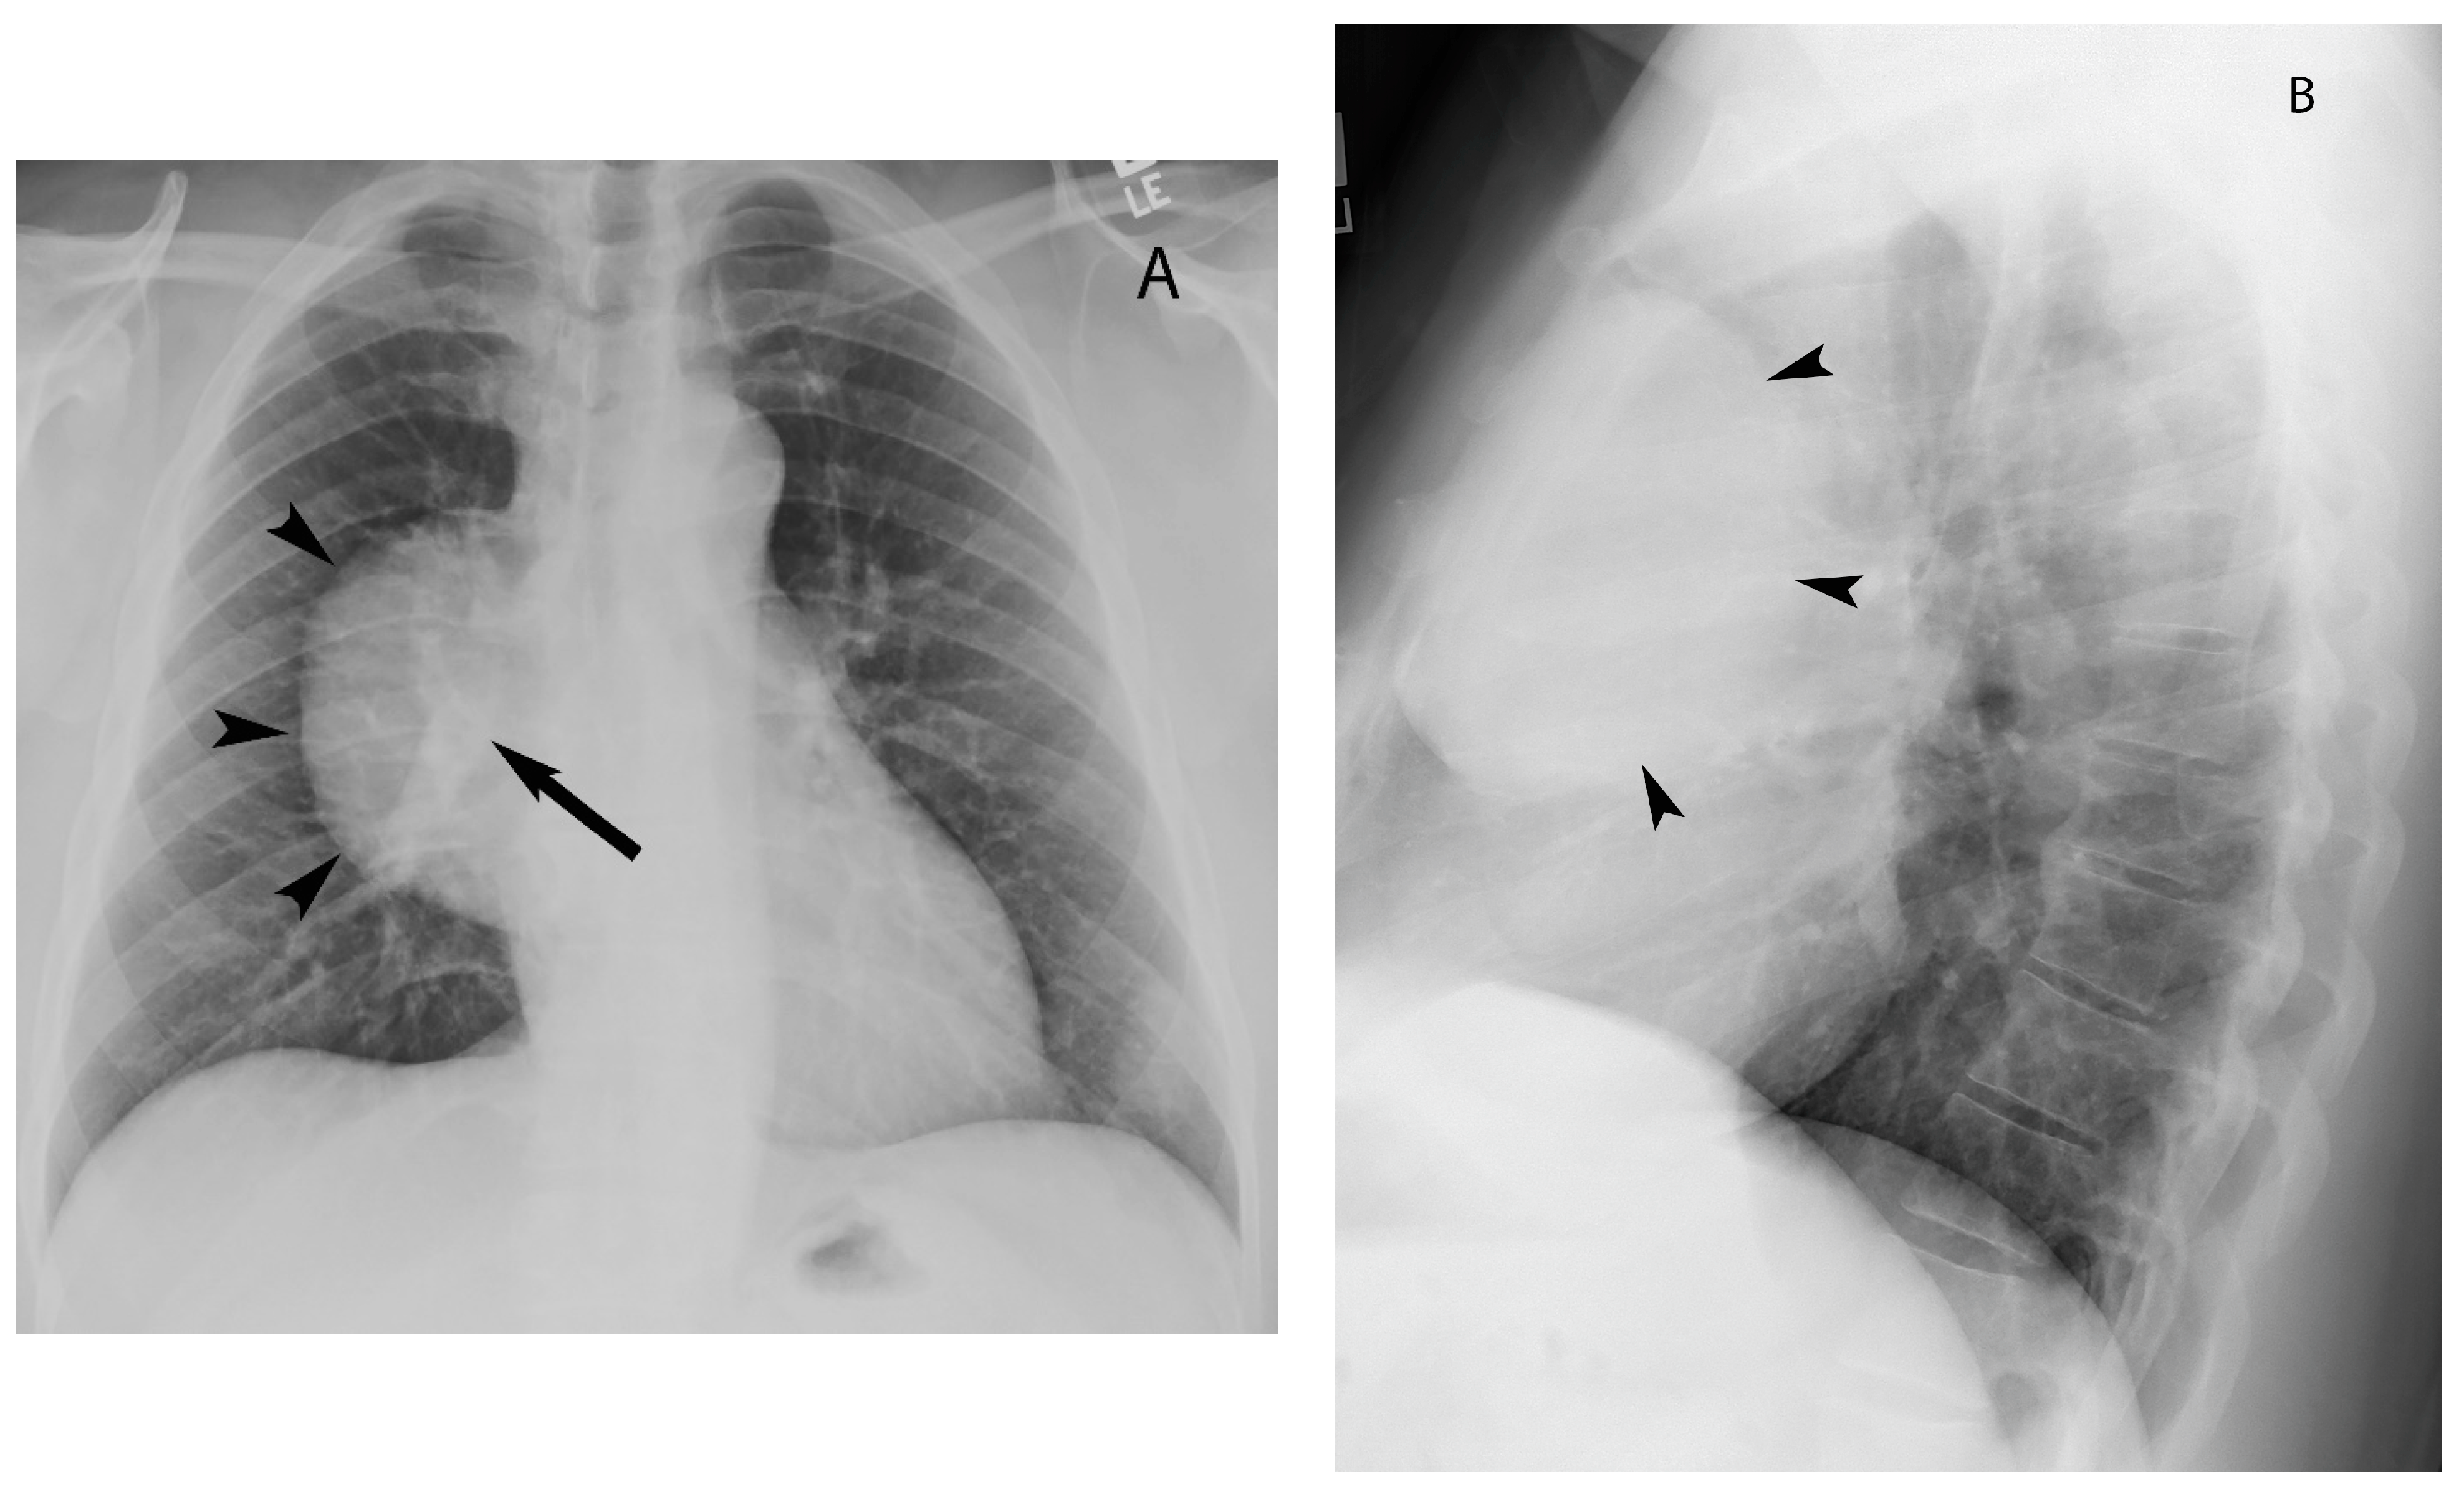

Visceral (Middle) Compartment

8. Cystic Lesions